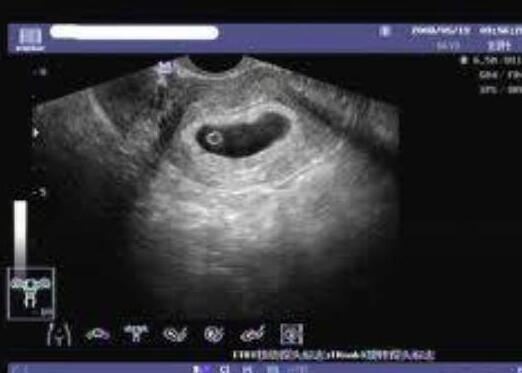

多囊卵巢综合征(PCOS)是一种常见的不孕症,其中一个重要的病理特征是多囊卵巢的形成,即多腔房的卵巢的存在。该病的发病率高达10%-15%,特别是在20-35岁的妇女中,表现为月经紊乱、不孕症或复发流产等。